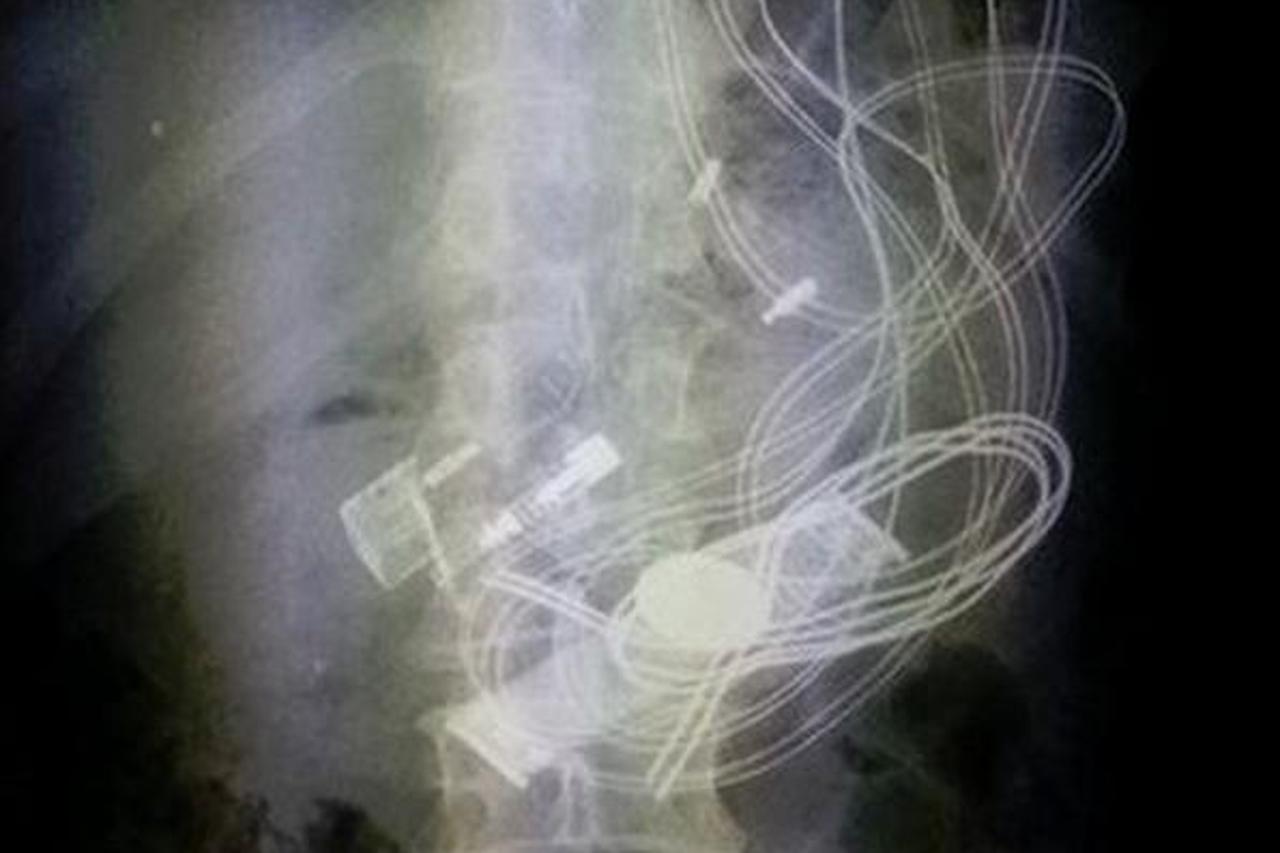

19 što je sve progutao?! Šokantna rendgenska snimka iz hrvatske bolnice! Pogledajte što su nedavno snimili liječnici Zavoda za radiologiju u jednoj hrvatskoj bolnici